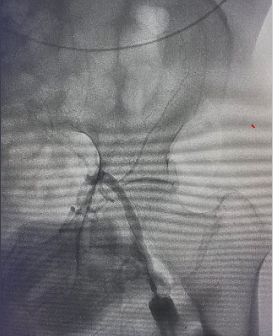

遂果断另辟蹊径,经肱动脉穿刺成功,行腹主动脉造影证实右侧髂总动脉闭塞,左侧髂总动脉极重度狭窄并串珠样改变,故经股动脉入路此路不通。

头颈部血管造影提示:患者为右侧颈内动脉极重度狭窄合并右侧大脑中动脉闭塞。

由远及近,优先开通右侧大脑中动脉恢复颅内血流,再行右侧颈内动脉起始部支架植入血管成形,顺利开通闭塞血管,颅内血流恢复。